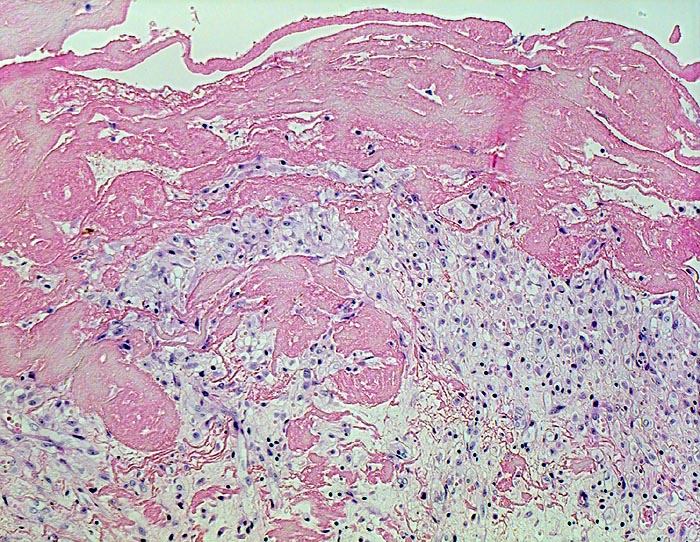

PathoPic ID 4534 - fibrinöse Perikarditis

fibrinöse Perikarditis

Entzündung / Reparatur

Perikard

Körperhöhlen, Serosa

Ein Teil des

Fibrins liegt dem Epikard auf, ein

Teil ist bereits inkorporiert in das organisierende Granulationsgewebe.

Patientin verstorben in Urämie.

Histologie

Vergrösserung

100